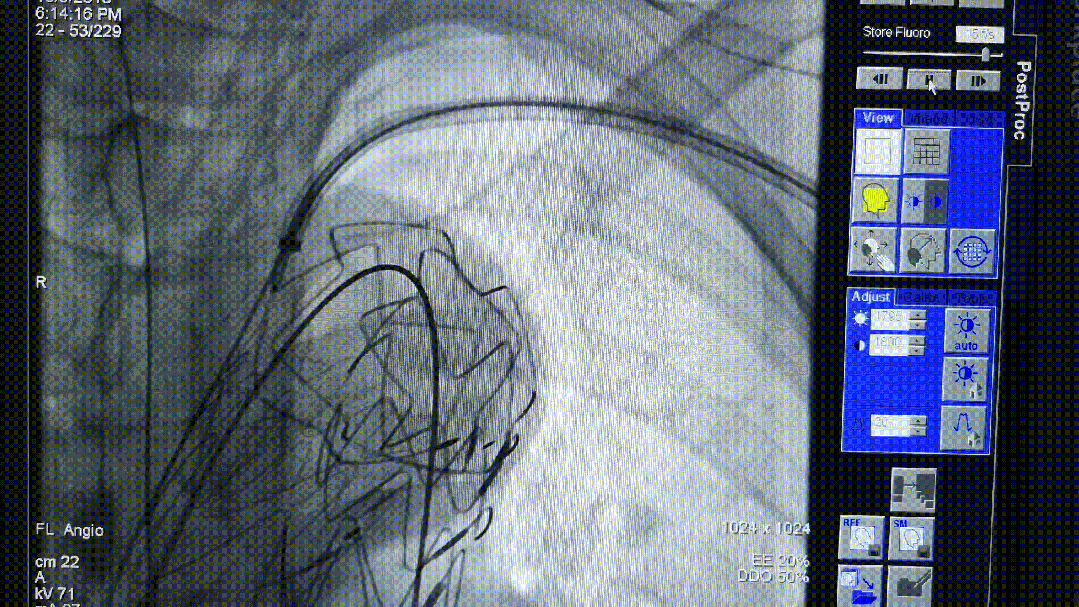

我们在两头35kg巴马公猪中完成动物实验:

成功实现弓上分支的快速、准确原位开窗;

破膜过程流畅,无分支或主动脉损伤;

取出标本可见圆形破口、支架贴合良好,证实技术可行性。

动物实验

巴马公猪35kg